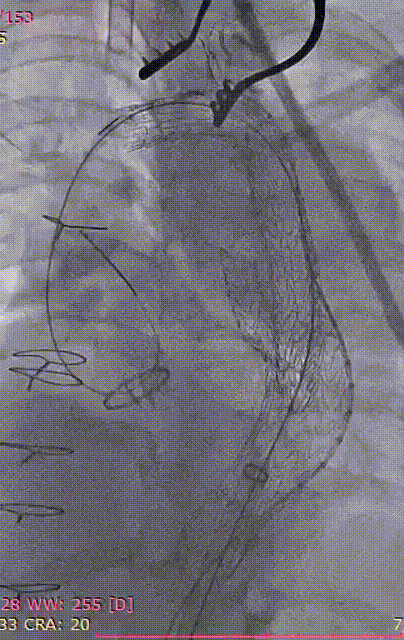

4. 继续送入近端GORE® TAG® 可主动调控胸主动脉覆膜支架TGMR313120,顶住导丝以左颈总后缘定位。

gore医疗怎么样「胸有乾坤」可调可控 精准出击——四川大学华西医院肖正华教授团队:CADS治疗B型主动脉夹层病例分享_https://www.jmylbn.com_新闻资讯_第22张

CADS支架定位

gore医疗怎么样「胸有乾坤」可调可控 精准出击——四川大学华西医院肖正华教授团队:CADS治疗B型主动脉夹层病例分享_https://www.jmylbn.com_新闻资讯_第23张

CADS释放前回撤鞘

5. CADS第一阶段释放,支架从近端向远端打开,释放至50%直径。

gore医疗怎么样「胸有乾坤」可调可控 精准出击——四川大学华西医院肖正华教授团队:CADS治疗B型主动脉夹层病例分享_https://www.jmylbn.com_新闻资讯_第24张

6. 支架近端位置微调后,再次顶住导丝,二次释放。

gore医疗怎么样「胸有乾坤」可调可控 精准出击——四川大学华西医院肖正华教授团队:CADS治疗B型主动脉夹层病例分享_https://www.jmylbn.com_新闻资讯_第25张

术中小弯侧定位造影

gore医疗怎么样「胸有乾坤」可调可控 精准出击——四川大学华西医院肖正华教授团队:CADS治疗B型主动脉夹层病例分享_https://www.jmylbn.com_新闻资讯_第26张

CADS释放一半后近端位置调整

7. CADS第二阶段释放,继续将超硬导丝顶紧大弯侧,释放CADS支架,支架由远端向近端打开至全直径,锁线钢丝全程将支架与输送系统进行固定,支架释放过程无移位,释放后,支架小弯侧贴附良好,无“鸟嘴”;最终造影可见隔绝良好,无内漏。

gore医疗怎么样「胸有乾坤」可调可控 精准出击——四川大学华西医院肖正华教授团队:CADS治疗B型主动脉夹层病例分享_https://www.jmylbn.com_新闻资讯_第27张

CADS第二阶段释放

gore医疗怎么样「胸有乾坤」可调可控 精准出击——四川大学华西医院肖正华教授团队:CADS治疗B型主动脉夹层病例分享_https://www.jmylbn.com_新闻资讯_第28张

CADS完全释放后造影